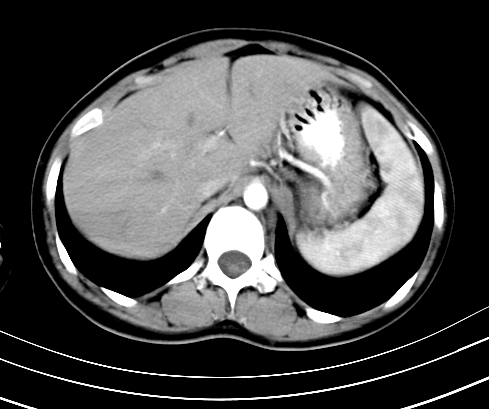

动脉期

静脉期